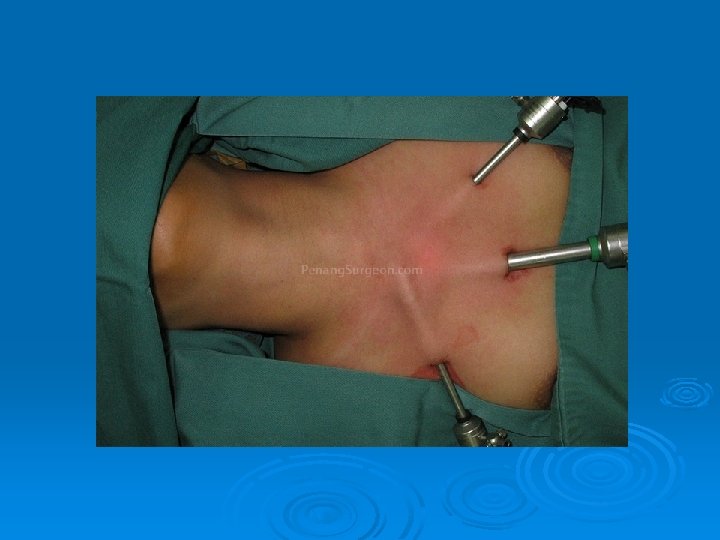

Minimally invasive parathyroid surgery

Minimaly inavsive parathyroid surgery Ø Ø Ø Videoendoscopic- co 2 insufflations Videoendoscopic- gassless Videoassisted Radioguided Focused central mini incision Focused lateral mini incision